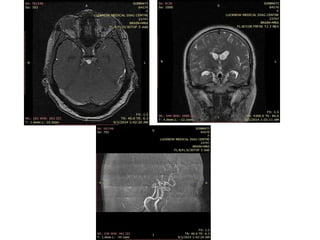

• #70 23 yr young female presented with post partum rt hemiparesis with altered sensorium, on improvement had aphasia, T2 and flair show multiple hyperintensities in lt parietooccipital region, corrosponding ,with restrictn on DWI and low ADC value s/o infarctn, corrosponding MRA , lt MCA not visualised s/o thrombosis.